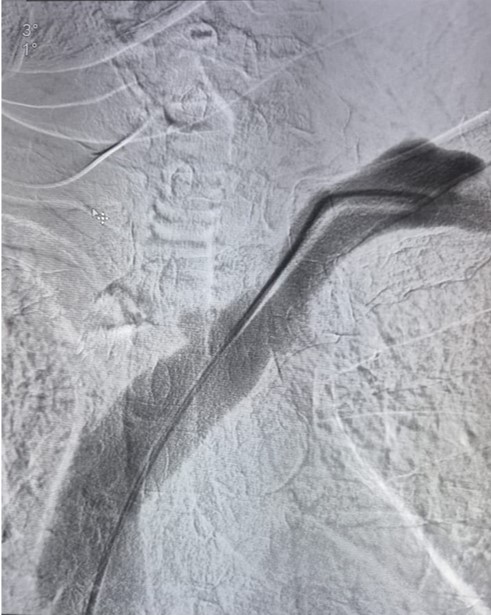

PRE VENOPLASTY

POST VENOPLASTY